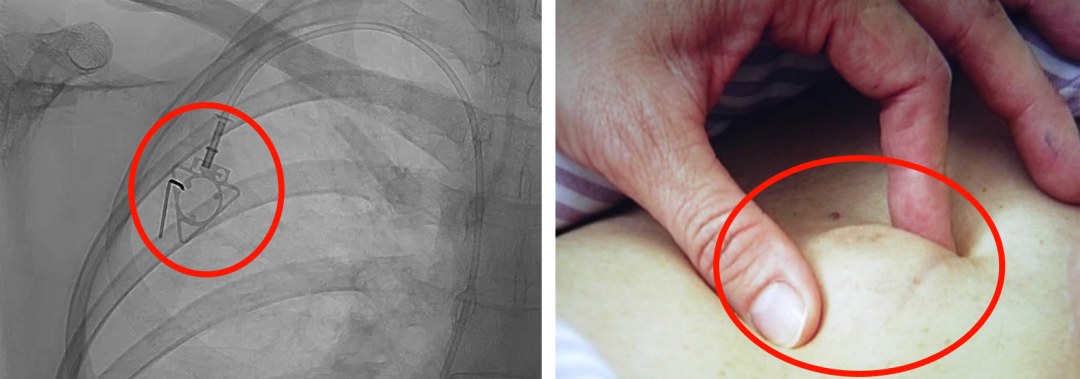

輸液港,臨床上也稱為PORT,是為了減輕藥物對(duì)患者血管刺激而置入體內(nèi)的專業(yè)輸液裝置。它分為三部分:無損傷針、置入靜脈的導(dǎo)管、埋藏在皮下與輸液針連接的注射座(港體)。注射座連接插入大靜脈的導(dǎo)管形成長期血管通路,發(fā)揮類似港口的作用,故稱作“輸液港”。

(1)輸液港輸注藥物直達(dá)大血管,手臂不會(huì)產(chǎn)生明顯的不適。由于每次穿刺的是皮下置入的港,可以減少針頭對(duì)血管的刺入次數(shù),操作簡(jiǎn)單,對(duì)患者的血管起到保護(hù)作用;

(2)輸液港放置在皮下,不易被別人發(fā)現(xiàn),具有隱秘性;洗澡,日常生活不受限制;

(3)由于輸液港完全埋藏在體內(nèi),不易受到感染;